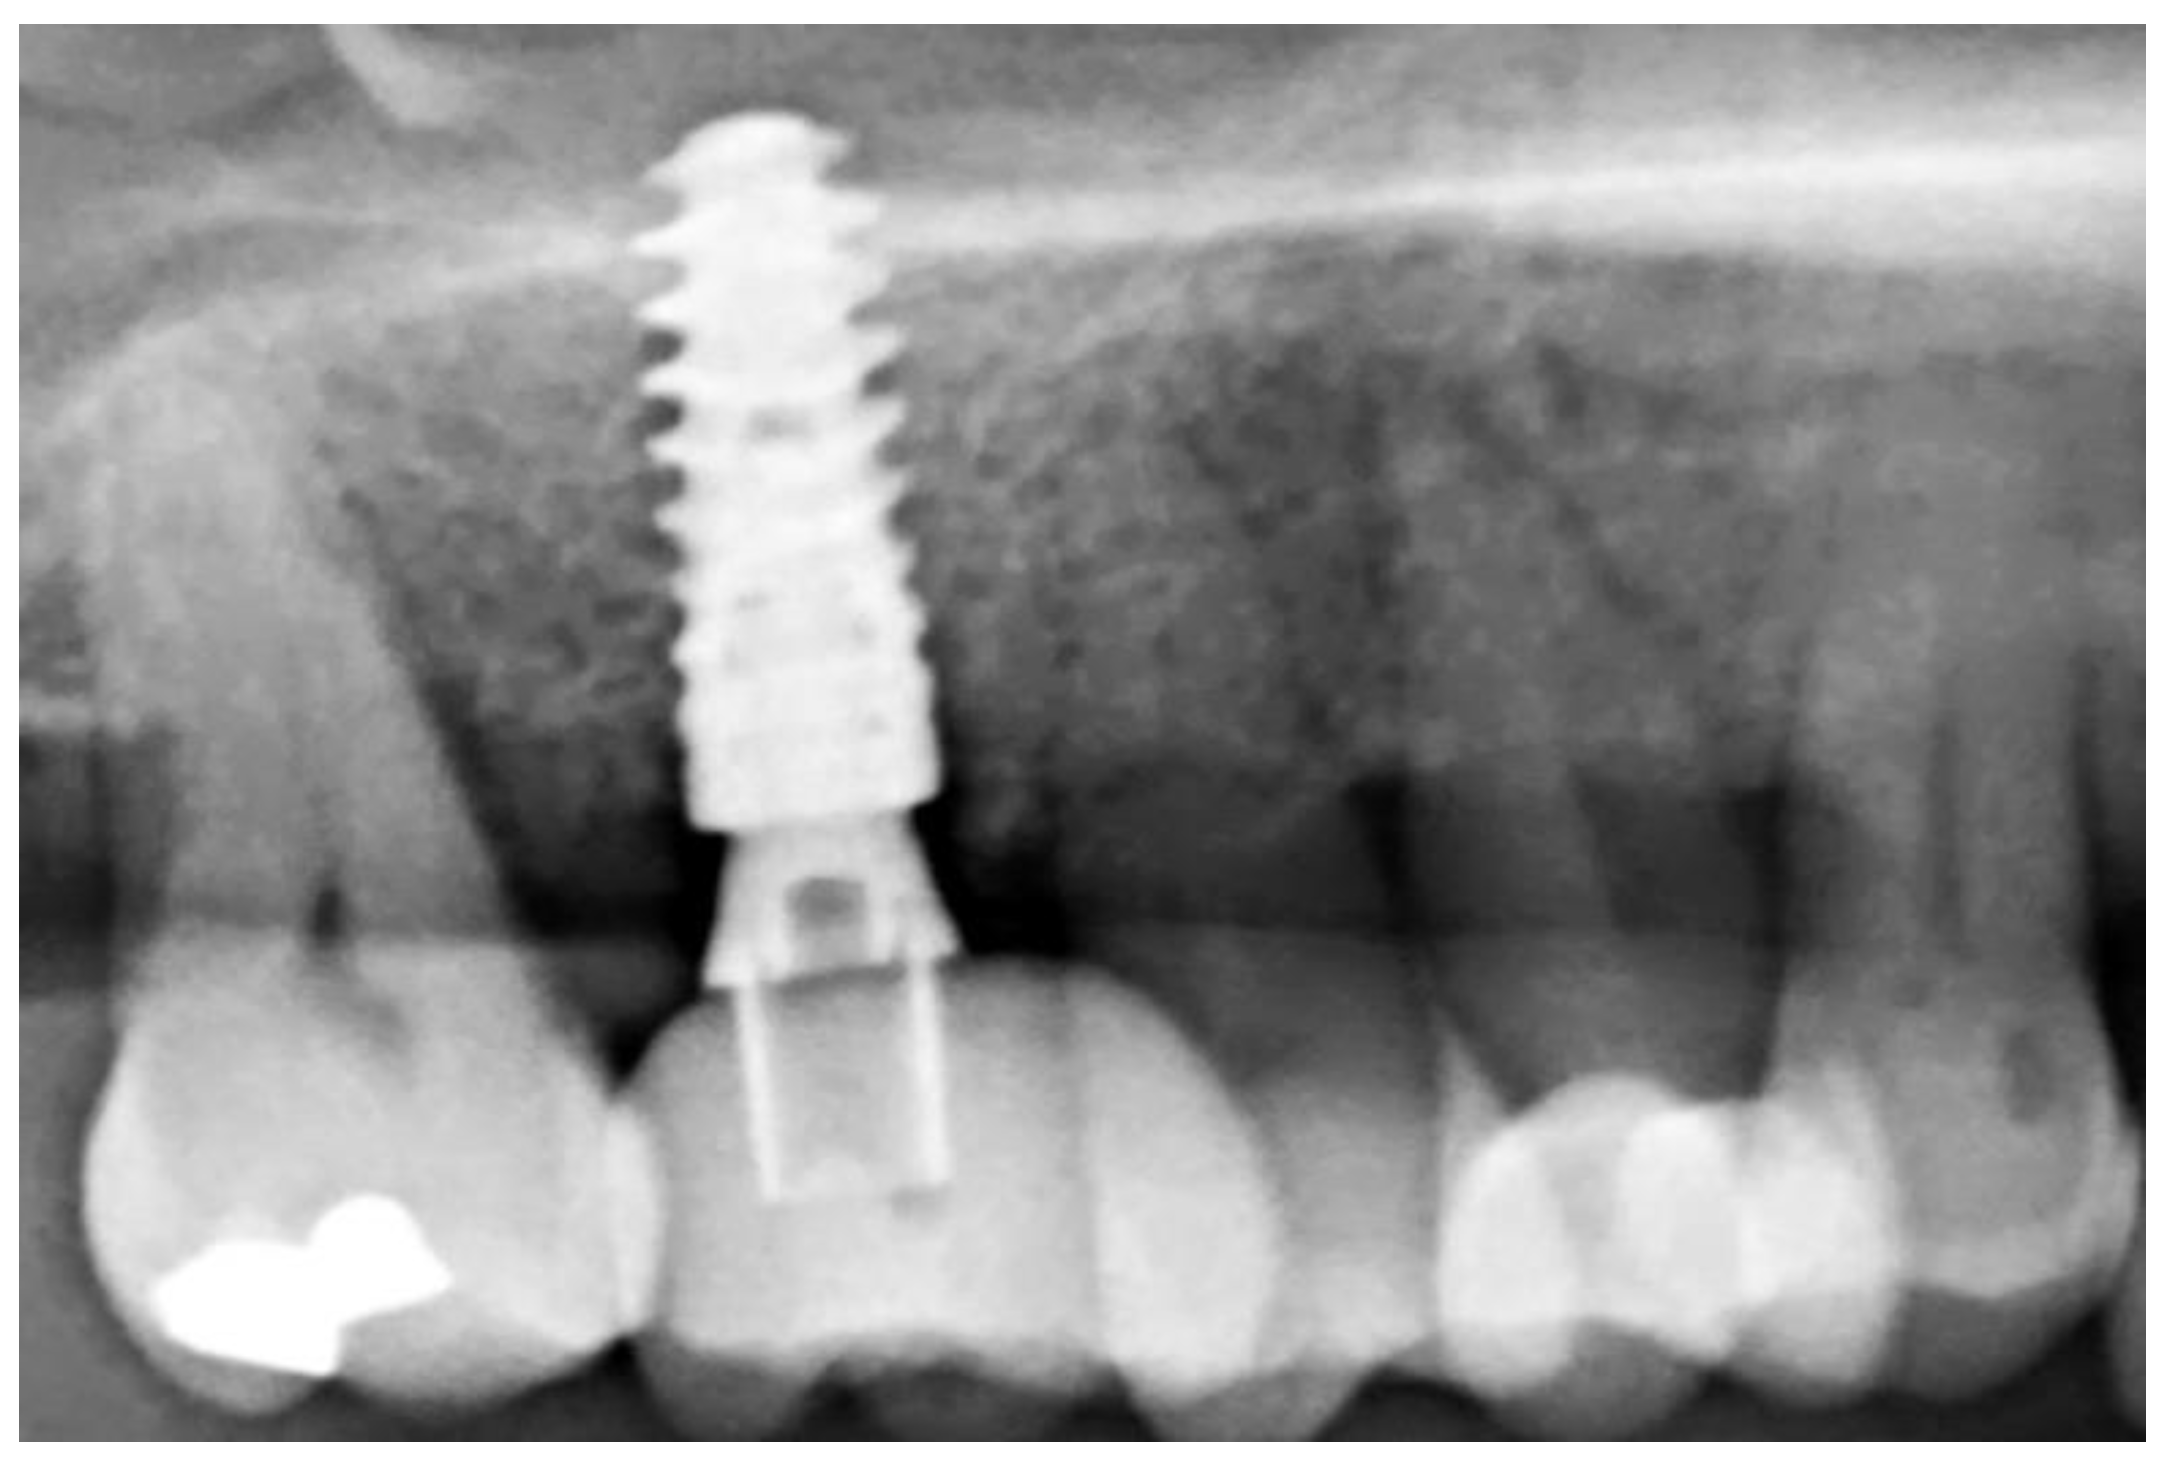

3.2. Ridge Dimension